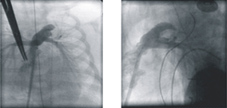

混合手術後血流可留至肺動脈